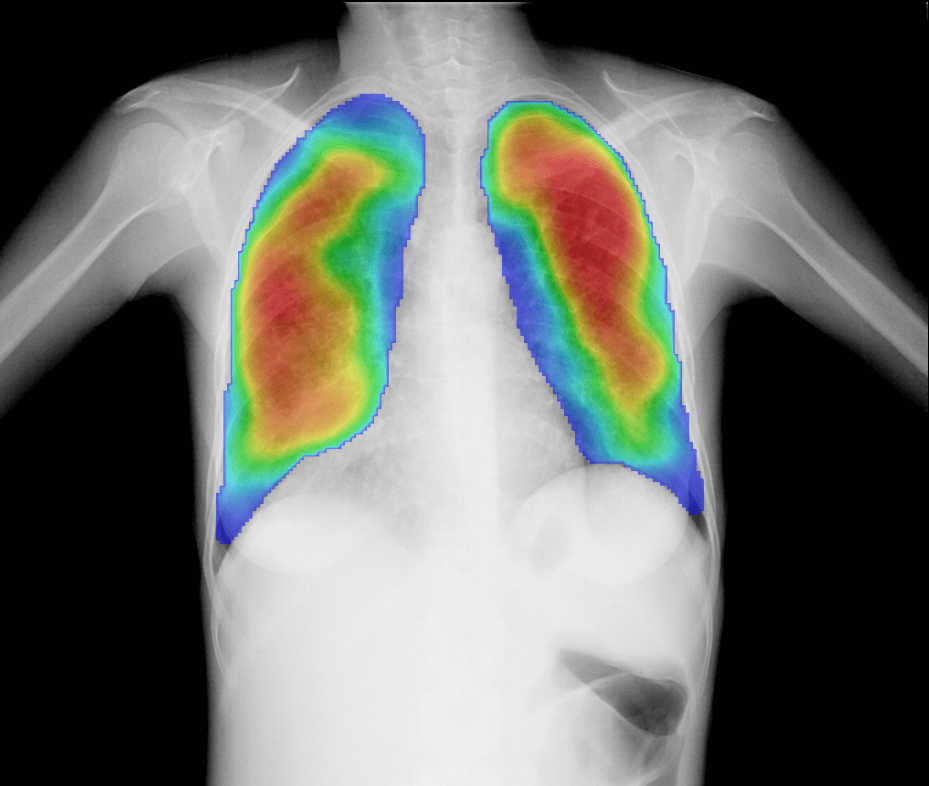

CAD4TB is rigorously validated software designed to assist users in swiftly, accurately, and cost-effectively detecting presumptive TB.

Proven to outperform trained human readers